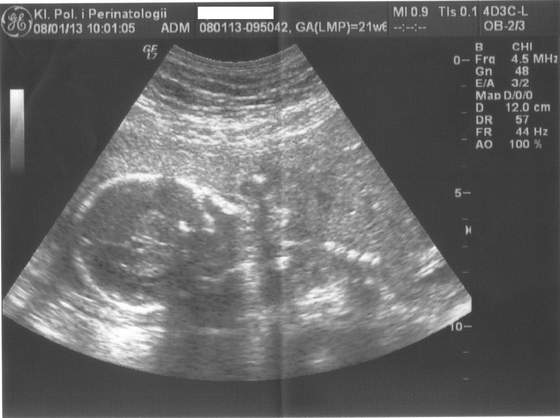

Przedstawiam Wam mojego prawdopodobnie syneczka:

zdjjj.jpg :-p